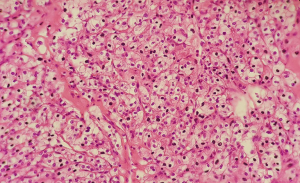

A male patient, 51 years old, native of Manaus, reports dysuria and polyuria associated with constant fever episodes and urinary tract infections with improvement by using several antibiotics but returning the symptoms after suspending it; evolving over a year with left flank and back pain and spreading out to the left inguinal region and testicle associated with anemia displayed at routine exams. The patient reports a surgical treatment 12 years ago for treating a staghorn calculus in the right kidney with similar symptoms, at the time in another hospital, but without further medical assistance after the procedure, even though claiming an improvement of the symptoms. He denies drug allergies, familiar history of calculus and cancer or any other comorbidities. He confirmed that after the first episode of staghorn calculi, he increased water intake, but did not maintain the same way over time. Six months after the beginning of his condition, during an ambulatory visit, it was requested a complete abdominal tomography with emphasis in the urinary system, blood and urine tests for clinical association, in addition to non-steroidal anti-inflammatory medicines. The patient return was in a month and no improvement of the pain in the patient’s feeling, with the tomography image tests result showing atrophy in the right kidney, which presents dilatation of the collector system, that it’s filled with material with density varying between thick liquid and soft parts (average of 45 UH), in addition to calculus in the pelvis and ureteropelvic junction, suggesting a pattern for xanthogranulomatous pyelonephritis and matching previous history of right staghorn calculus (Figure 1). The left kidney presented normal dimensions, exophytic nodule in the lower pole measuring 3.4 cm × 2.8 cm with contrast enhancement similar to renal parenchyma, associated with a simple cortical cyst and a large staghorn calculus (6.0 cm × 3.5 cm) in this kidney, with average density of 300 UH, 7.7 cm distant from the pelvis, causing dilatation of superior caliceal group in this kidney. Presented abnormal test results for urea with 109 mg/dL and creatinine with 4.4 mg/dL. It was decided for partial left nephrectomy and total right nephrectomy, considering that it had significant hydronephrosis, a relevant decrease in the parenchyma and, mainly, being an infectious focus. The patient also had history of several episodes of urinary infection resistant to antibiotics, presenting potential risk of sepsis. The incision made was bilateral subcostal, followed by exploration and control of right renal hilum. The right kidney presented with hydronephrosis, although with rigid consistency and intense inflammatory process. Total right nephrectomy was performed. After that, partial left nephrectomy began, with isolation and controlling of the left renal hilum vessels, performing for excision of the renal nodule of the upper pole, followed by anatrophic nephrolithotomy with Brödel’s line incision, that revealed great purulent discharge escape (about 500 milliliters) (Figures 2-4). Staghorn calculus was removed with double-J stent implanted in left ureter and layer suture performed. The surgery went through eight hours and was attended by nephrology service of the same hospital. In the following four days after the procedure, the patient was maintained under observation in the intense therapy unity, performing dialysis every two days, with progressive improvement of the pain and operative wound with great appearance. The left renal function showed constant increasing during the dialysis. On the fifth post-operative day, the patient returns to the urology nursery care with renal function still impaired but presenting diuresis of 1,500 milliliters per day on average. In the seventh day presented obvious hematuria by Foley catheter, needing a successful bladder washing. The patient was discharged from hospital in the 12th post-operative day with pain improvement and clear renal function progress, not needing continuous post-operative dialysis. The anatomopathological examination of the left kidney showed renal cell carcinoma, clear cell type, with nuclear grade of Führman 1, measuring 25 cm in larger diameter (5) (Figure 5). The right kidney just showed hydronephrosis without neoplasms signs.